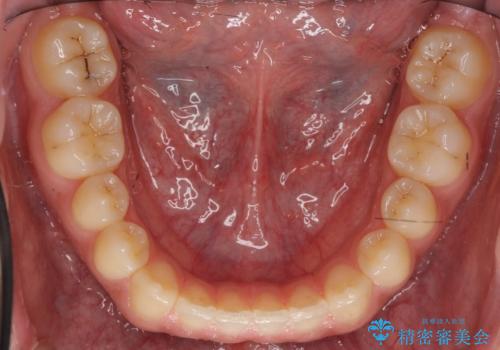

- 前歯のすき間を気にして来院。

受け口もあり、前歯が端同士であたる、切端咬合となっていました。

下の歯のすき間を閉じて上の歯の内側に入るように位置付けました。

すき間もきれいに閉じ、満足していただきました。

上の前歯は下の歯と直接へりが当たっていた状態(切端咬合)だったため、形がいびつだったのは、わずかにやすりがけをして整えました。

セラミックですき間を閉じようとすると、すきまをうめるために巨大な歯になり、また、下の歯が前に出て強く当たるため、セラミックがかけるおそれがあります。また、下の歯をさけようとすると角度をかえるために歯を極端に削らなければならなくなり、神経をとらなければいけなくなるリスクもあります。

このような歯並びは、セラミックでかぶせるよりは、矯正治療の

適応と言えます。